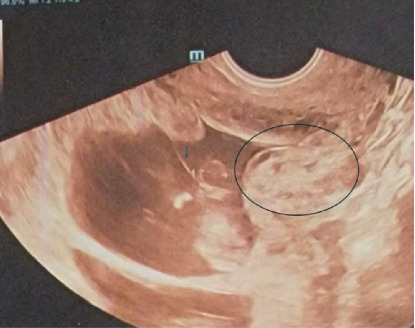

Abstract Image